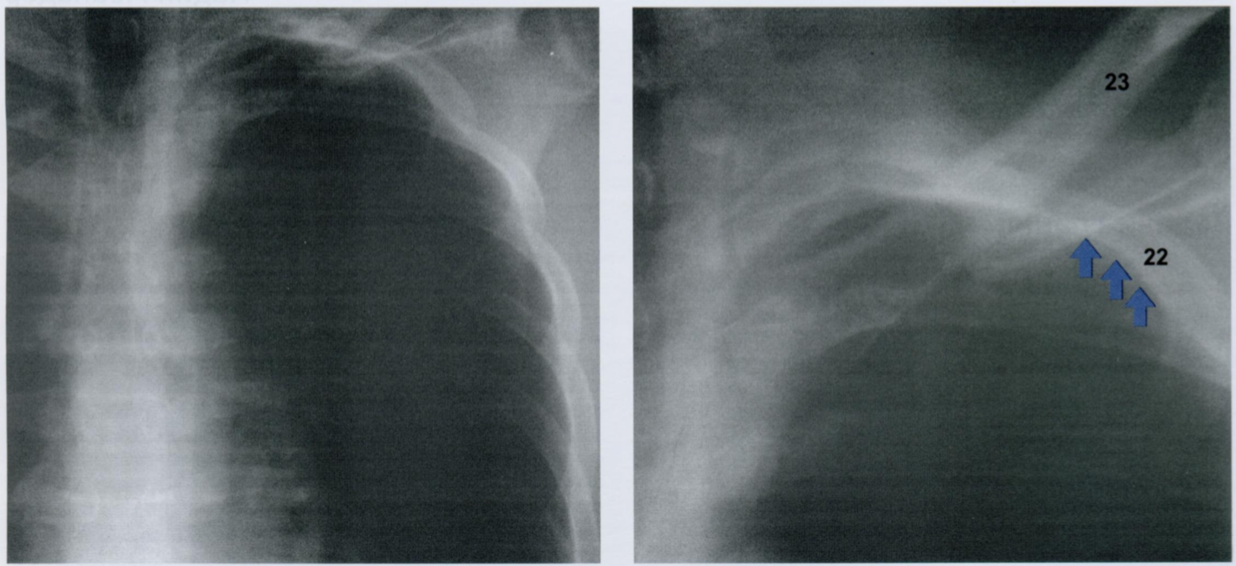

На снимке контурной стрелкой показана «парааортальная полоска», образованная за сердцем тенью плевры, примыкающей к нисходящей аорте (8). Подобная картина наблюдается и в области верхушек. Плевральная линия выглядит, как продолжение заднего сегмента второго ребра с каждой стороны в медиальном направлении. Обе линии соединяются над дугой аорты (6), образуя вертикальную линию.

На рентгенограмме в БП по заднему краю трахеи (14) определяется ретротрахеальная полоска (закрашенная стрелка). Кроме того, в базальных отделах (12) - загрудинная полоска (контурная стрелка). Эта полоска образуется за счет жировой клетчатки эпикарда, и ее не следует путать с участком уголщенной плевры.

Кроме того, париетальная плевра хорошо видна несколько выше, где она выглядит, как волнистая линия из-за периодических вдавлений в межреберные промежутки. В норме плевра выглядит как тонкая, гладкая, ровная линия.